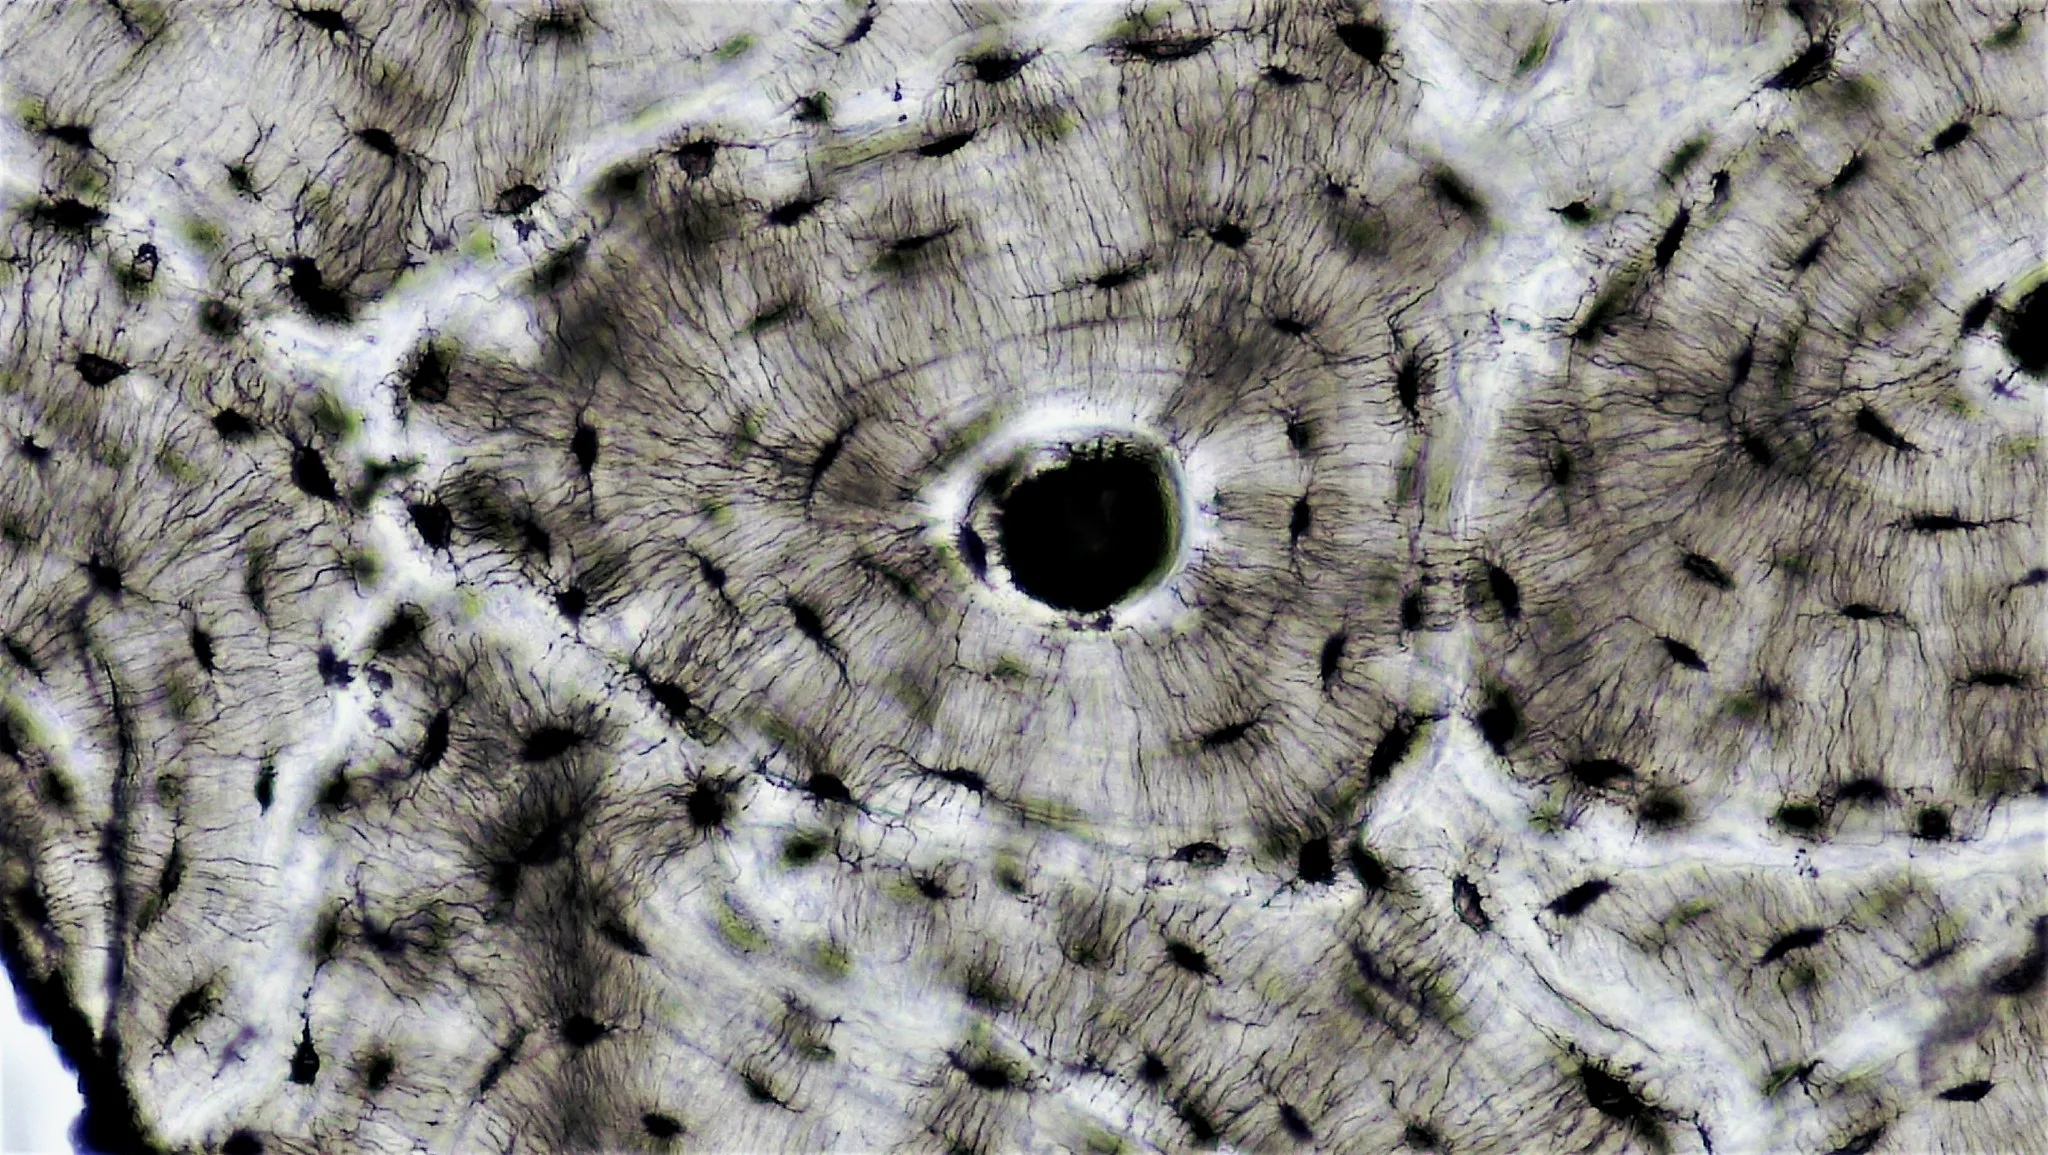

Sezione istologica dell'osso corticale — canale di Havers, lamelle concentriche e osteociti

Ogni osso compatto del corpo umano è costruito intorno a migliaia di cilindri concentrici chiamati osteoni. Al centro di ciascun osteone corre un canale — il canale di Havers — che ha un diametro medio di circa 50 micrometri e contiene tutto ciò che serve per mantenere vivo il tessuto circostante: capillari, venule postcapillari, precapillari e, in alcuni casi, fibre nervose amieliniche.

Le lacune osteocitarie sono piccole cavità scavate tra le lamelle. Ogni lacuna ospita un osteocita — la cellula sentinella dell’osso. Gli osteociti comunicano tra loro e con il canale di Havers attraverso prolungamenti citoplasmatici che corrono in sottili tunnel chiamati canalicoli. Questa rete — il connettoma osteocitario — è il sistema nervoso dell’osso: percepisce le sollecitazioni meccaniche e coordina il rimodellamento.

La linea cementante è il confine esterno dell’osteone: una sottile banda di matrice ipermineralizzata che lo separa dagli osteoni adiacenti e dall’osso interstiziale. Studi recenti dimostrano che la linea cementante ha un ruolo cruciale nella propagazione delle microfratture — le devia, impedendo che attraversino l’intero osso.